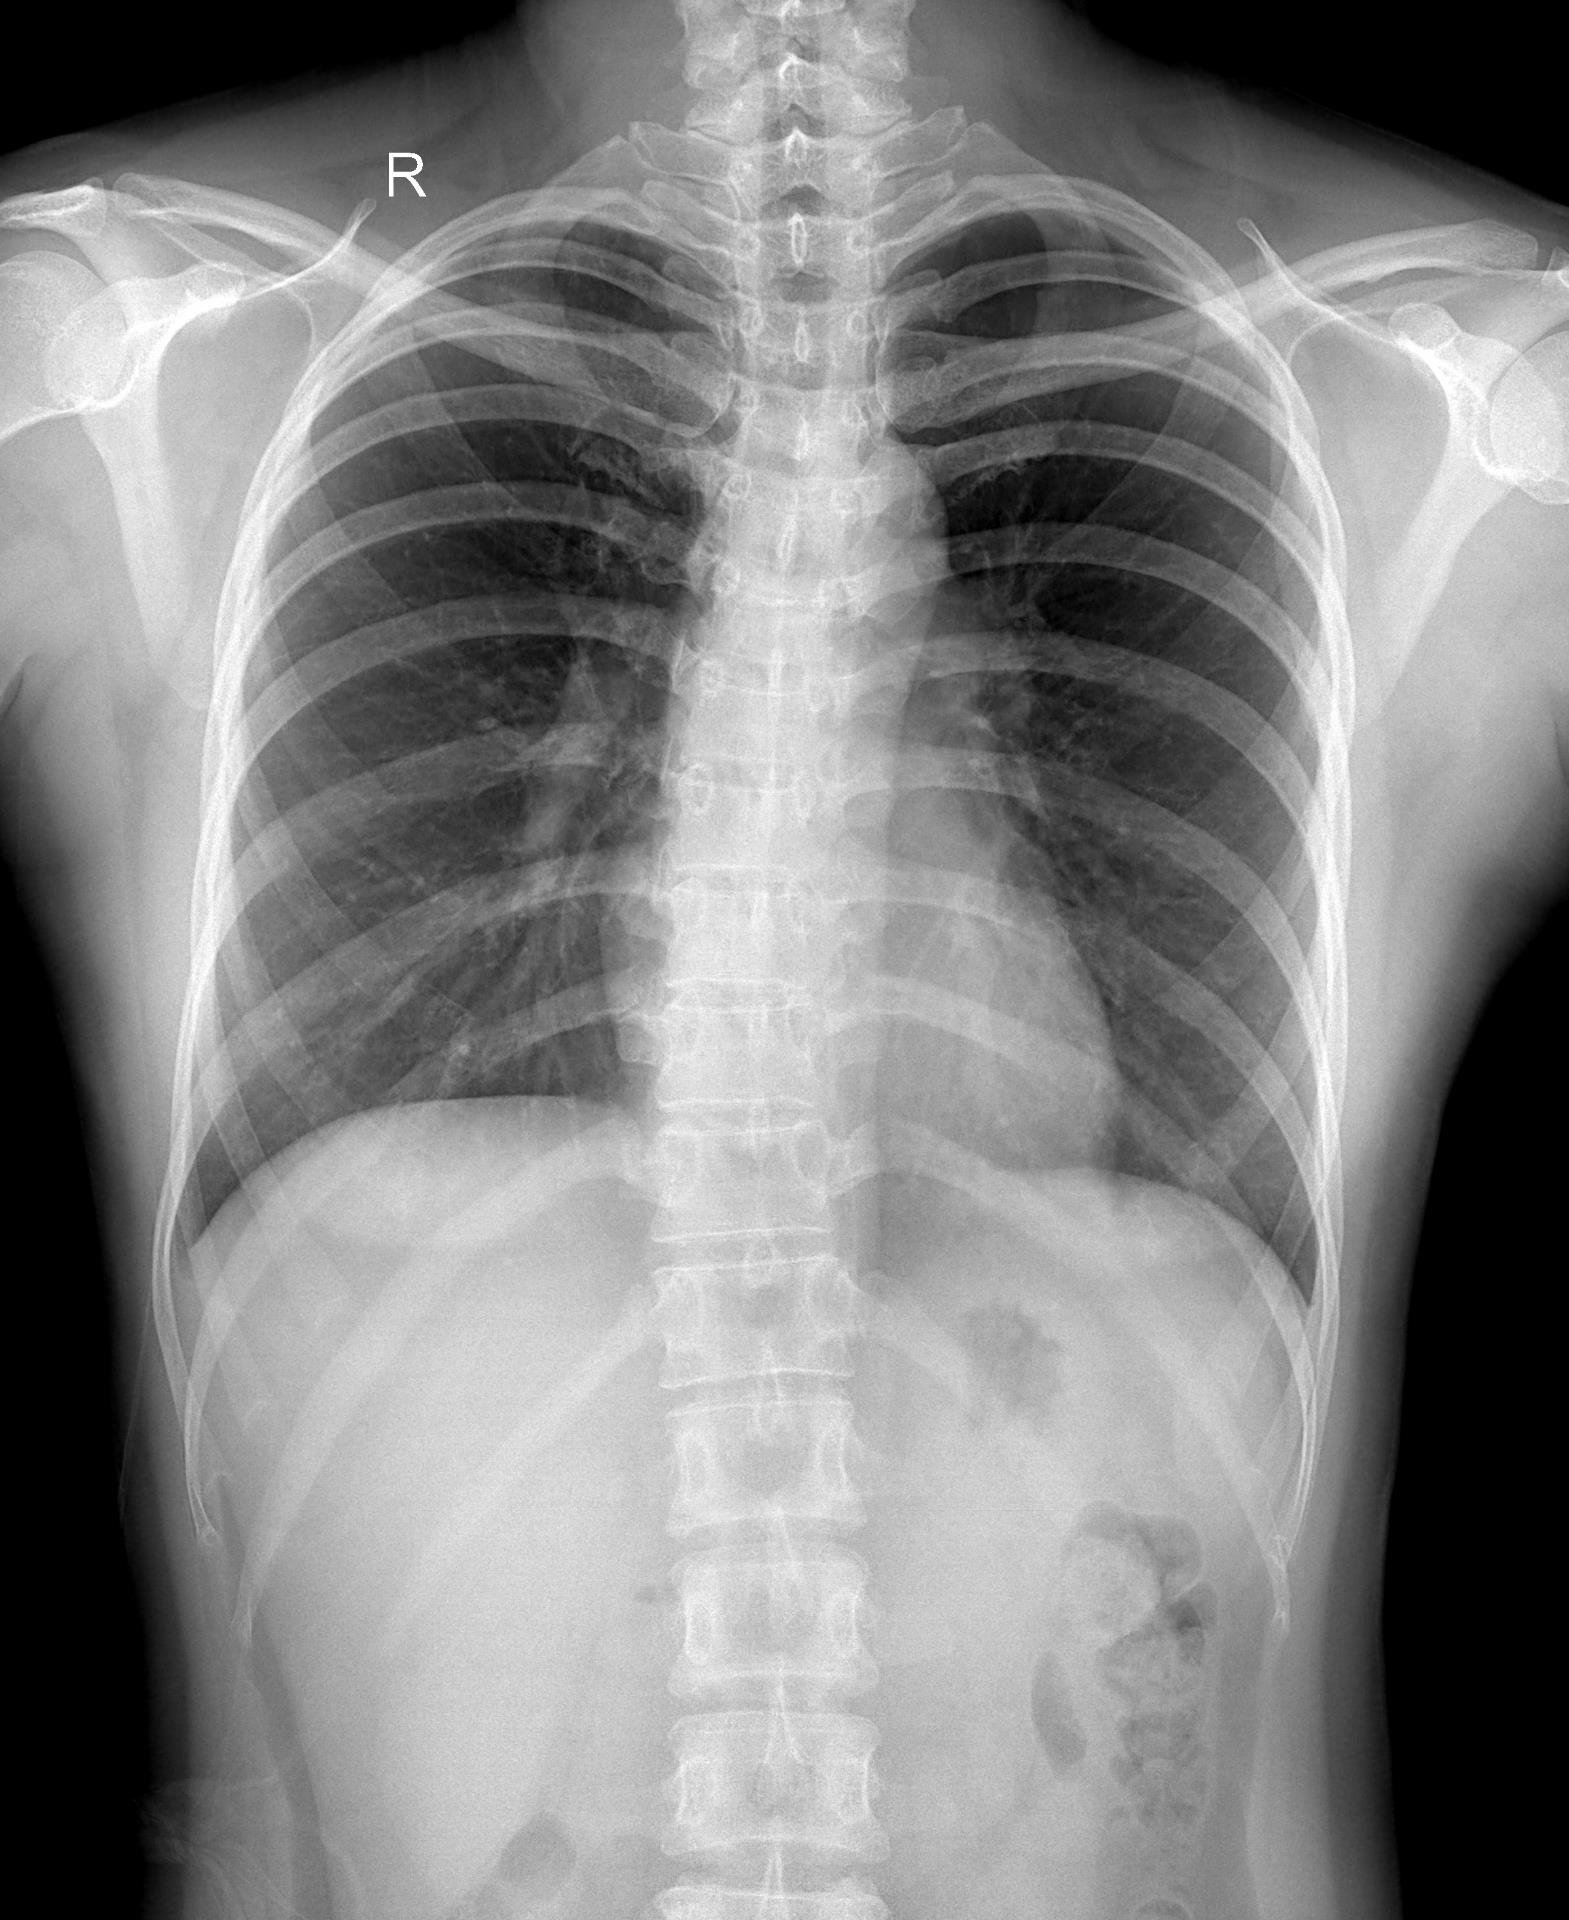

Chụp X-quang cột sống là kỹ thuật sử dụng tia X để ghi lại hình ảnh cấu trúc xương của cột sống, bao gồm các đốt sống cổ, ngực, thắt lưng và xương cùng. Với X-quang cột sống toàn phần, bác sĩ có thể quan sát cột sống như một chỉnh thể thống nhất, thay vì chỉ nhìn từng đoạn riêng lẻ.

Chụp X-quang toàn bộ cột sống là phương pháp chẩn đoán hình ảnh giúp bác sĩ đánh giá tổng thể cấu trúc xương sống, từ đó phát hiện sớm nhiều bất thường và bệnh lý quan trọng. Thay vì chỉ quan sát từng đoạn riêng lẻ, kỹ thuật này cho phép nhìn cột sống như một chỉnh thể thống nhất, phản ánh đúng trục chịu lực và sự liên kết giữa các vùng cổ – ngực – thắt lưng – xương cùng.

Hệ thống máy X-quang hiện đại, cho hình ảnh rõ nét, liều tia được kiểm soát an toàn.

Đội ngũ bác sĩ chuyên khoa giàu kinh nghiệm trong chẩn đoán cơ xương khớp.

DHA Healthcare với hệ thống máy móc hiện đại, cho hình ảnh rõ nét, tia liều được đảm bảo.